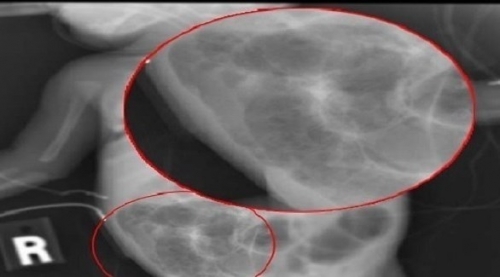

وحالياً يُشخص المرض بالأشعة السينية، شرط أن يكون ذلك بشكل متكرر، لمراقبة المرض بمجرد الاشتباه فيه، لسرعة تطوره المثيرة للقلق.